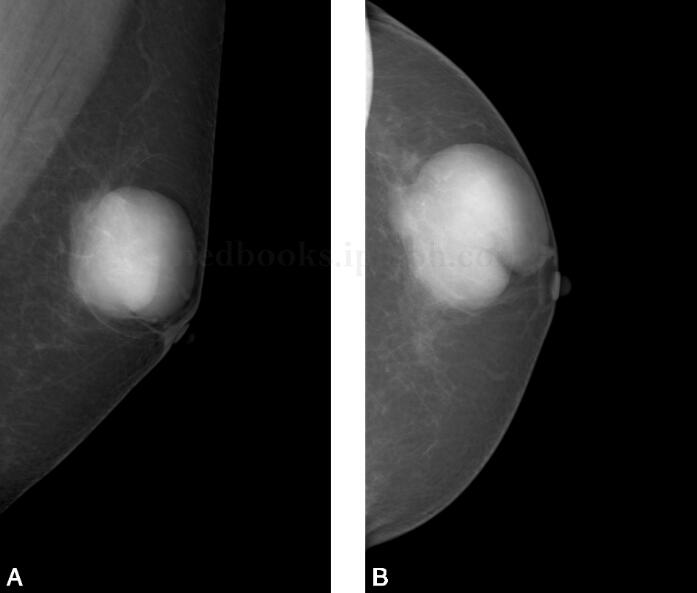

图1 左乳轴斜位片

左乳腺脂肪型,外上象限见边界清楚肿块影,大小约4.5cm×4.2cm,局部见较深切迹